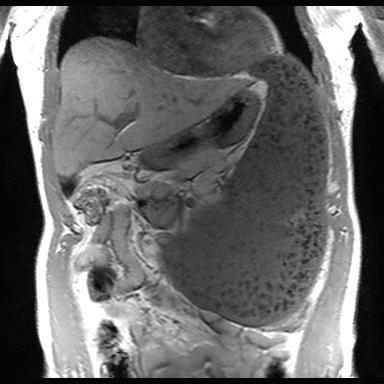

They are typically rounded or sessile nodules, and have density and enhancing characteristics similar to the rest of the spleen, or expected density of the spleen if there has been a splenectomy.

MRI

Signal characteristics are similar to normal spleen 2

T1: hypointense

T2: hyperintense

T1 C+ (Gd): heterogeneous enhancement